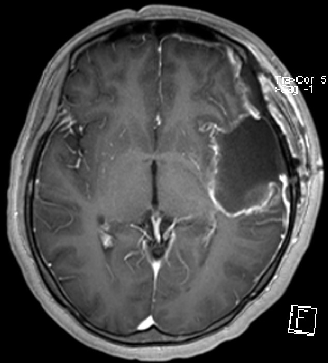

真倒霉这人颅内竟同时长了两个肿瘤

结果:1,间变型星形细胞瘤 2,脑膜瘤